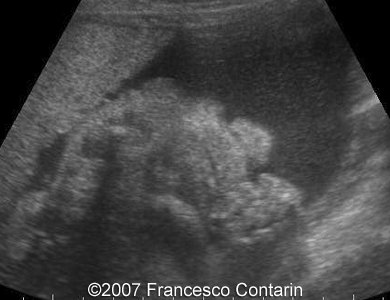

This is a 22-year-old woman (G4, P2) with unremarkable familiar history, referred to our hospital at 29 weeks of gestation due to a fetal ascites. There were no signs of maternal-fetal blood incompatibility. The ultrasound investigation revealed rhizomelia, postaxial polydactyly, small thorax, short ribs, ascites, increased abdominal biometric parameters, polyhydramnios. We supposed two diagnoses: Short rib-polydactyly syndrome versus Jeune syndrome (asphyxiating thoracic dystrophy).

Images 9, 10. 29th week of pregnancy -  fetal ascites (left); and transverse plane through narrow thorax (right).

9

10